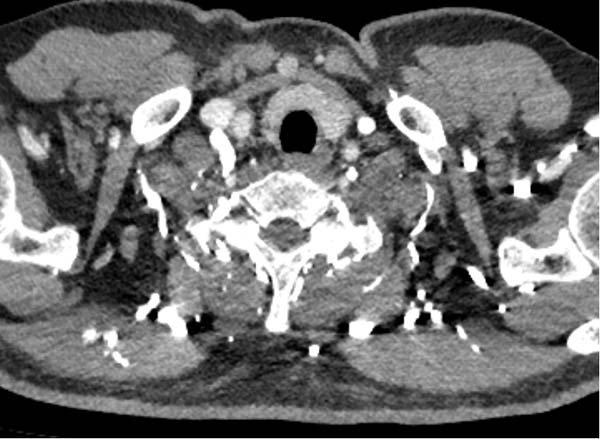

四、特殊情况下留置针穿刺位置的调整

留置针穿刺时并非总是右手原则,还要综合考虑患者的血管条件、是否存在损伤风险、急重症患者的操作便利等情况。在条件允许、保证图像质量情况下尽量首选穿刺右上肢肘正中静脉。特殊情况,需更换为左侧穿刺:

4) 右侧上肢血管畸形或闭塞。

右锁骨下堵塞导致肺动脉充盈欠佳